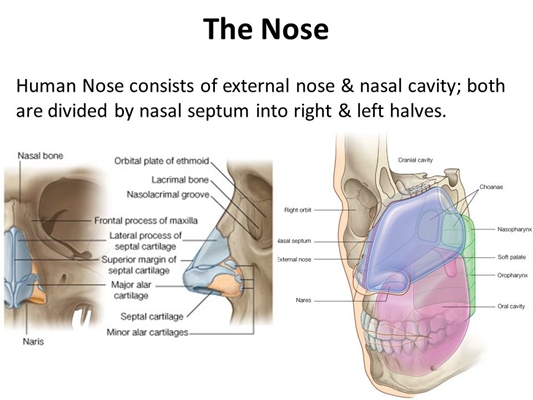

鼻中隔彎曲手術圖解 (5)

鼻中隔彎曲手術圖解 (50)

鼻中隔彎曲手術圖解 (6)

鼻中隔彎曲手術圖解 (43)